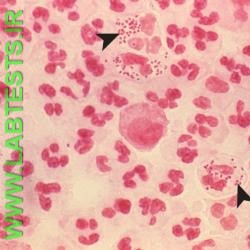

- Whether there are bacteria present within other cells (intracellular)

- Presence of red blood cells or white blood cells

- Gram-negative cocci—Neisseria meningitidis causes meningitis while Neisseria gonorrhoeae causes the sexually transmitted disease gonorrhea.

Samples such as blood and cerebrospinal fluid are generally sterile. Bacteria are not usually present in these samples when there is no bacterial infection. Bacteria may initially be present in low numbers with an infection, and this type of sample may require extra processing in order to concentrate the bacteria so that they can be detected by a Gram stain.

Other body fluids and sites, such as sputum or skin, typically have cells and normal flora present in addition to any bacteria that are causing an infection. Gram stains on these types of samples require careful examination by a trained laboratorian to determine which cells may be normal and which may be due to an infection.